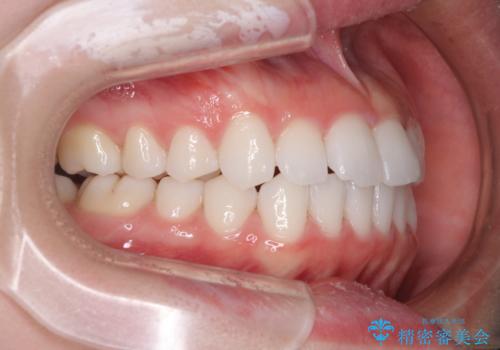

治療開始から4ヶ月ほどで概ね歯列が整い、その後の3ヶ月で細かい部分を仕上げていきました。

短期間で綺麗に仕上がり、患者様には大変満足していただきました。